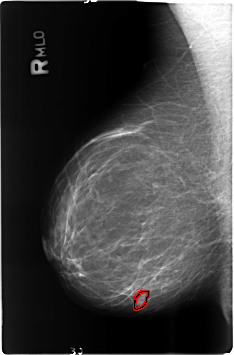

B_3482_1.RIGHT_MLO

RIGHT_MLO LINES 4608 PIXELS_PER_LINE 3032 BITS_PER_PIXEL 12 RESOLUTION 50 OVERLAY

FILE: B_3482_1.RIGHT_MLO.OVERLAY

TOTAL_ABNORMALITIES 1

ABNORMALITY 1

LESION_TYPE MASS SHAPE OVAL MARGINS CIRCUMSCRIBED-ILL_DEFINED

ASSESSMENT 4

SUBTLETY 2

PATHOLOGY BENIGN

TOTAL_OUTLINES 1

BOUNDARY